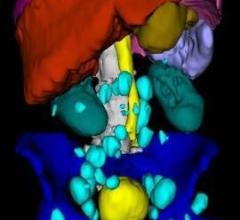

November 24, 2009 – Version 2.0 of a software application for the detailed analysis of lymph nodes allows the user to conduct side-by-side comparison and temporal tracking of images taken at different stages of lymph node development.

Biotronics3D is rolling out several new clinical applications at RSNA 2009, including the launch of a thin-client version of its flagship 3Dnet advanced visualization software. The company said its software helps increase workflow by enabling the enterprise to use 3D tools integrated with its PACS everywhere. Biotronics3D said its software easily integrates into any PACS.

November 20, 2009 – A new service for endovascular specialists who treat aortic aneurysms converts 2D computed tomography (CT) axial images to 3D images of the anatomy and aneurysm measurement for device sizing, precase planning and patient follow-up.

November 20, 2009 - Advanced visualization software is increasingly coming embedded in PACS. One new platform recently available to radiologists provides native MPR and 3D packages in all PACS workstations. Volume visualization aims to increase productivity and improve service level to referring physicians.